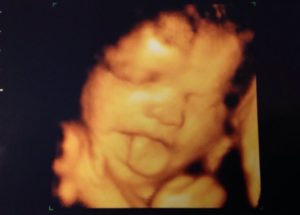

В этот период беременности можно наблюдать в процессе УЗИ эмоциональную активность плода, а также рассмотреть первые движения ребенка, его способность сосать палец. После ультразвуковой диагностики мама получит симпатичное фото своего крохи.

Усовершенствование мозга плода, а также его нервных окончаний продолжается на 31 неделе развития. Малыш становится очень чувствительным к этому времени, это заметно даже во время третьего УЗИ.

Если вкус ребенку нравится, то на его лице появляется улыбка (которую так любят наблюдать будущие родители), а если нет — ребенок недовольно кривится.